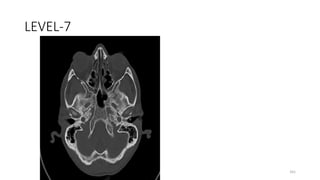

LEVEL-7

161

CAROTID CANAL

162

CLIVUS

163

Foramen lacerum

164

FORAMEN OVALE

165

FORAMEN SPINOSUM

166

Jugular foramen becoming sigmoid sinus

167

INFERIOR ORBITAL FISSURE

168

Jugular tubercle of occipital bone (roof of

hypoglossal canal)

169

Occipital bone, squamous part

170

Occipitomastoid suture

171

Petroocipital fissure

172

Petrosphenoidal fissure

173

Pterygopalatine fossa

174

BODY SPHENOID

175

GREATER WING SPHENOID

176

SPHENO SQUAMOUS SUTURE

177

TYMPANO SQUAMOUS FISSURE

178

PETROUS TEMPORAL

179

TYMPANIC PART OF TEMPORAL

180

SQUMOUS TEMPORAL